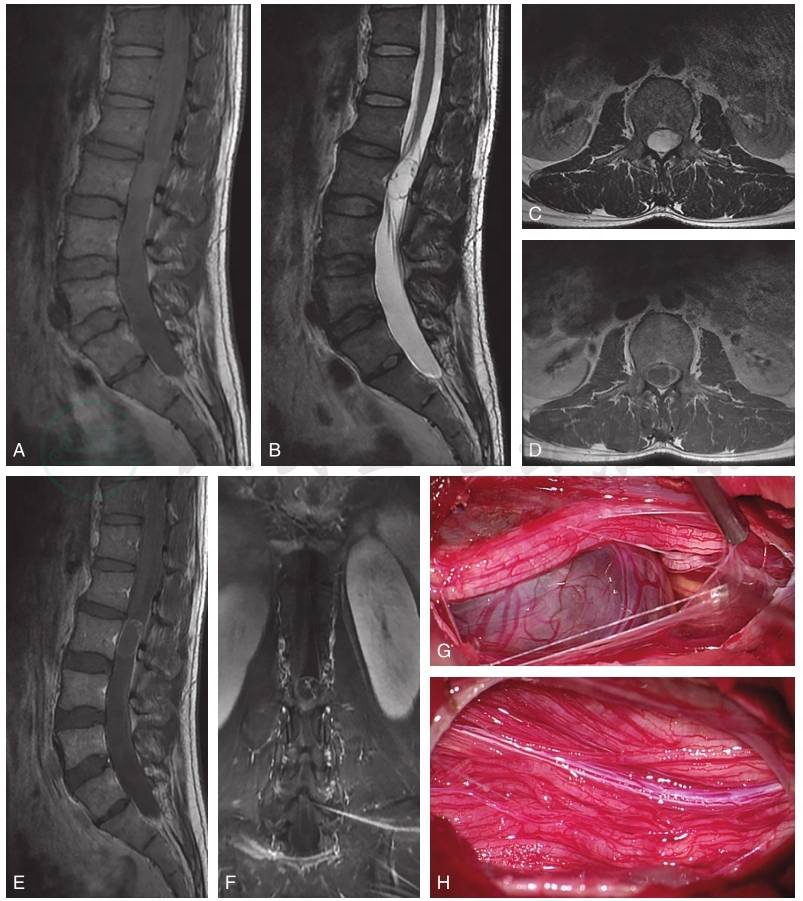

图4L3椎体水平囊变的神经鞘瘤

腰椎MRI显示L3椎体水平占位性病变,T1(A)加权像矢状位呈等信号,T2加权像矢状位(B)和轴位(C)呈高信号,T1增强像轴位(D)、矢状位(E)和冠状位扫描(F)可见病变外壁及内部分隔呈明显强化,内可见小结节强化。术中(G、H)可见病变呈囊性,病变腹侧及背侧马尾神经根明显受压、移位、充血、水肿。

引自:周围神经外科学.第1版.ISBN:978-7-117-33415-0.主编: